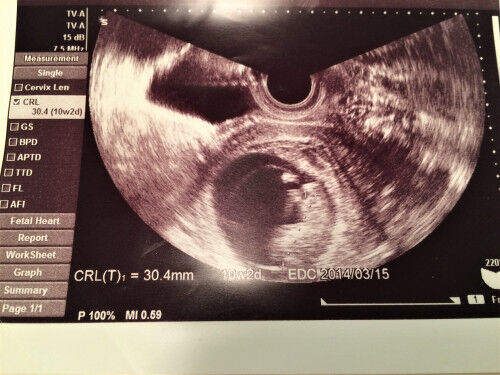

妊娠10カ月生期産 (妊娠37週~41週)に入ると胎児は 胎外での生活の準備が整いいつ生まれても良い状態になります 長いようで短かったようにも思われる妊娠期間妊娠10週目の胎児のエコー写真を見ると、赤ちゃんの大きさは、頭殿長(CRL)が31~42mm、体重は5~8g程。 手足首の関節もできあがり、手足をバタバタさせる様子を見せることも。 ピークを過ぎてつわりが軽くなる、終わる人も出てくる一方、まだつわりがひどいという人も。 お腹の膨らみの実感はまだないでしょう。 ネット検索の中で「9週の壁」「10週の壁」と妊娠10・11・12週目に胎動(赤ちゃんの動き)を感じるか? 妊娠10~12週目で胎動を感じることは、ほぼないねん。 胎動を感じられるのは妊娠中期である16週目から27週目の間くらい。 妊娠10・11・12週目で妻に頭痛がする原因について

これは先ほど説明した 胎児の推定体重を、「胎児発育曲線」グラフに当てはめて判断しています。 胎児発育曲線グラフとは、正期産(37週~41週のお産)で生まれた 正常な体重の赤ちゃんの胎児時代の推定体重データを元に、 妊娠週数ごとの基準値、つまり平均値をグラフ化したものです。胎齢 56→62日 赤ちゃん(CRL) 29→38cm 胎のう(GS) 58→66cm 10週0日から出産予定日まで210日 10週6日から出産予定日まで4日妊娠10週目・赤ちゃんの首の後ろの浮腫(nt)を指摘される 妊娠10週の妊婦健診のことでした。 その日もいつもと同じ流れでエコーをしてもらい、すぐに話を終えて帰れるかと思いきや 「赤ちゃんの首の後ろの浮腫が気になるね」